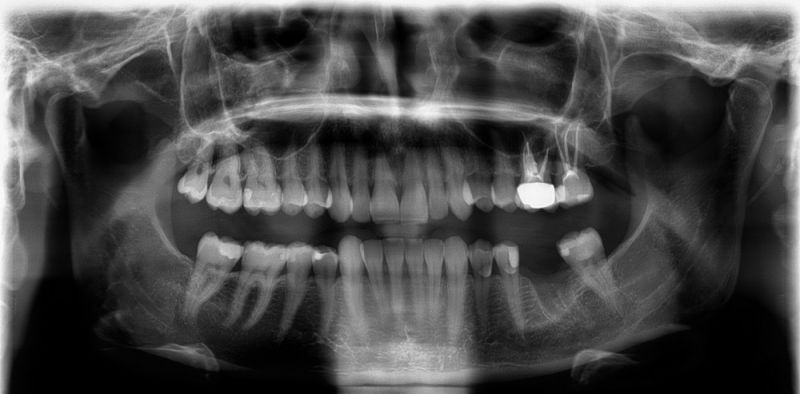

3 wuzelkanalbehandelte Zähne und einen gezogenen Backenzahn später wusste die Patientin, dass diese Beschwerden nicht durch Zähne verursacht wird, wie der damals behandelnde Zahnarzt vermutete.